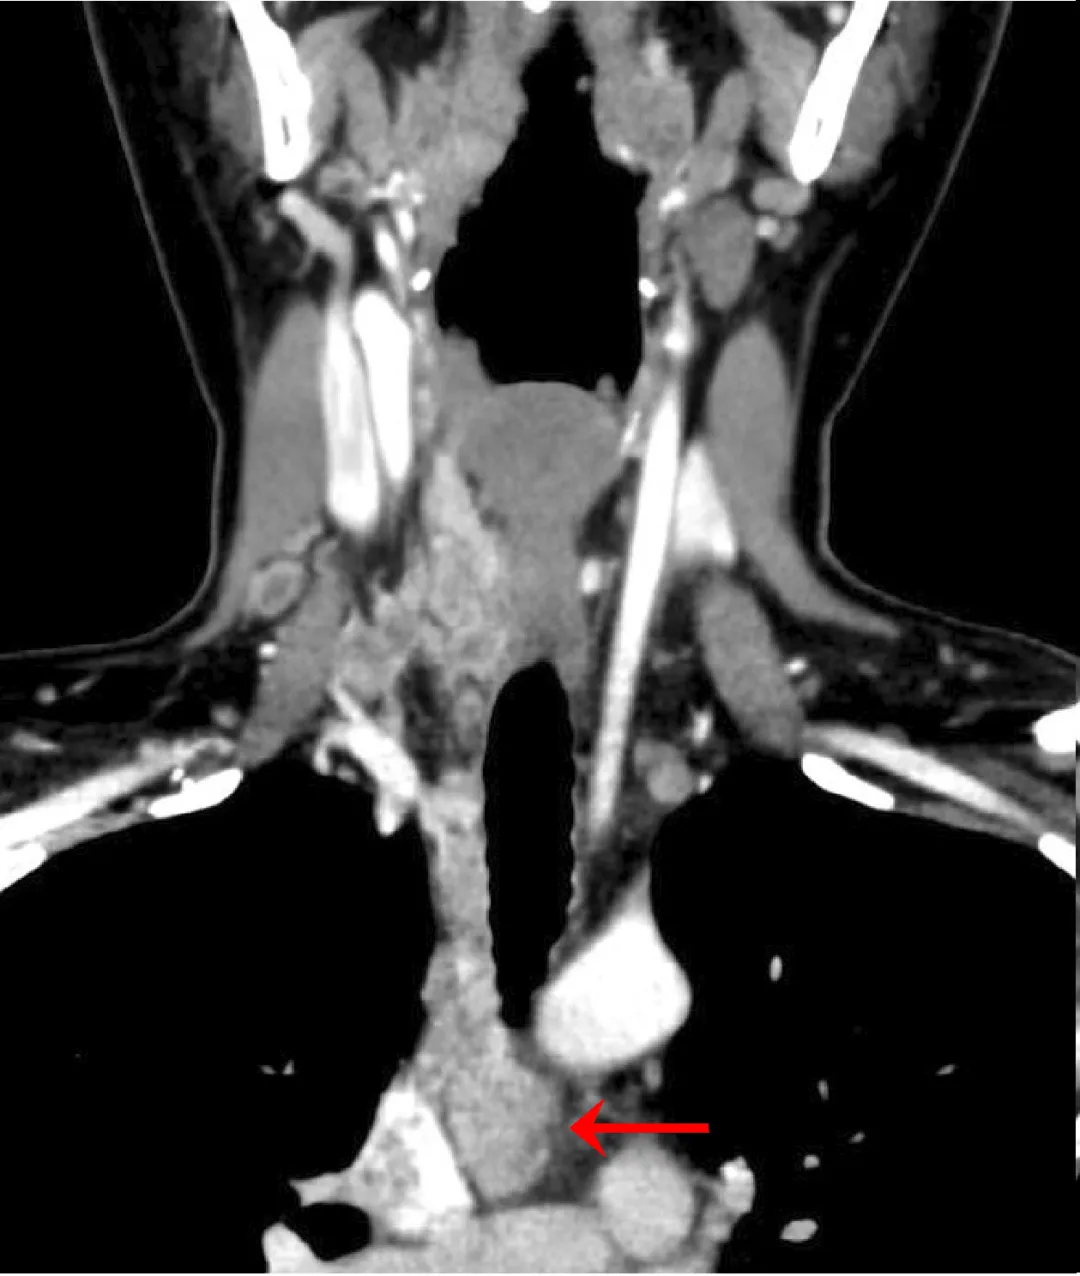

2025年9月,范女士在体检中意外发现甲状腺癌,进一步检查显示:双侧甲状腺癌已侵犯喉返神经、甲状旁腺及带状肌,并广泛转移至双侧颈部淋巴结、右侧锁骨上下区及纵隔淋巴结;肿瘤紧邻颈部及纵隔胸腔大血管,尤其心包内部分紧邻上腔静脉终末部及右肺动脉,周围重要神经、淋巴管等解剖结构也受到波及。

辗转多家医院后,范女士及家属深知手术风险极高:纵隔心包内肿瘤紧邻上腔静脉等大血管,即便劈开胸骨,术中剥离肿瘤时仍可能引发致命的大出血;肿瘤侵犯右侧喉返神经、甲状旁腺等重要结构,术后可能出现永久性声音嘶哑、终身补钙等后遗症,严重影响生活质量;术后还可能出现食管瘘、纵隔感染等继发问题,危及生命,其病情复杂程度远超常规。